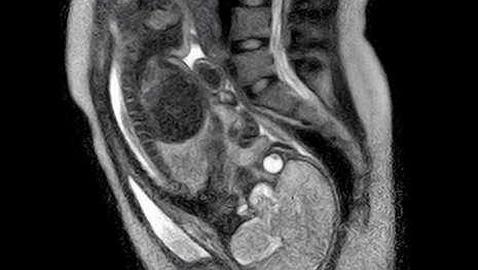

Se han filmado partos y algunos padres los han visto, pero por primera vez en la historia ha podido contemplarse en La Charité de Berlín el desarrollo y consumación de un parto desde dentro, a través de una resonancia magnética (MRT) abierta y retransmitida en varios monitores.

Un equipo combinado de médicos de obstetricia y radiología, de la histórica clínica universitaria de Berlín, ha grabado en su totalidad el alumbramiento, dejando abierta la sofisticada máquina de resonancias a fin de que la madre pudiera moverse con libertad durante el parto.

"Las imágenes son reamente fascinantes y vienen a probar una vez más que cada alumbramiento es todo un pequeño milagro", ha dicho Beinder a los medios. En las imágenes ya adelantadas, todo el movimiento en el útero de la madre es claramente visible, como así la dilatación progresiva de la pelvis.

Una resonancia, a diferencia de las radiografías, no entraña ningún peligro ni para la mujer ni para el niño. Sin embargo, la máquina fue apagada al romperse el saco amniótico para no dañar el oído del bebé.

La Charité ha empleado para el experimento una MRT que se abre como un sandwich, a diferencia de las habituales en forma de tubo. De este modo los ginecólogos y matronas han podido ayudar a la madre en todo momento. El proyecto pionero ha estado dirigido por los doctores Felix Güttler y Ulf Teichgräber.